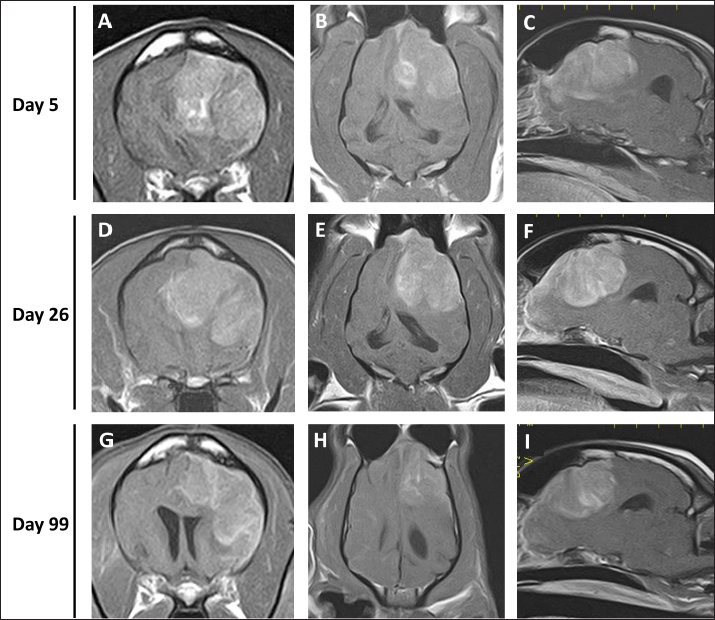

As intracranial disease was suspected in the present case, magnetic resonance imaging (MRI) using a 1.5 Tesla superconducting unit (Vantage Elan, Canon Medical Systems, Otawara, Japan) was performed as further investigation on day 5. MRI revealed a solid mass in the left frontal lobe that the lesion was 32.4 × 29.9 × 27.7 (length × width × height) mm in size showing homogeneous contrast enhancement that shifted the brain midline to the right in contrast enhancement T1-weighted image (T1WI) (Fig. 1A–C). Continuity with the meninges was observed at the tumor margin on contrast-enhanced T1WI. High-signal intensity findings in the brain parenchyma around the tumor indicate edema and/or inflammation on T2-weighted imaging (T2WI) and fluid-attenuated inversion recovery (FLAIR) images. Cerebrospinal fluid was not collected because increased intracranial pressure was suspected based on the MRI findings of transtentorial herniation. MRI findings indicated the possibility of meningioma or HS, and the owner requested surgical volume reduction and medical treatment with anticancer drugs. Radiotherapy was refused because of the cost, and prednisolone (PREDONINE tablets 5 mg; Shionogi & Co, Osaka, Japan) was prescribed at 1 mg/kg once a day until the operation. On day 26, an MRI examination was performed again, revealing that the lesion had grown to 34.7 × 29.9 × 34.9 mm (Fig. 1D–F). The next day, a surgical biopsy due to transfrontal craniotomy was performed to reduce intracranial pressure and confirm the diagnosis. The dog was premedicated with maropitant (1 mg/kg; Cerenia, Zoetis Japan, Tokyo, Japan), fentanyl (3 μg/kg; Fentanyl Injection 0.5 mg, Terumo Corporation, Tokyo, Japan), and lidocaine (2 mg/kg; Lidocaine Intravenous Injection 2%, Terumo corporation), all administered intravenously (IV). General anesthesia was induced with propofol (Propofol Intravenous Injection 1%, Maruishi Pharmaceutical, Osaka, Japan) to facilitate IV until intubation could be performed, following which propofol-based total intravenous anesthesia accompanied by constant rate infusions of fentanyl (10 to 15 μg/kg/hr) and medetomidine (1 to 3 μg/kg/hr; Dorbene, Kyoritsu Seiyaku Corporation, Tokyo, Japan) was administered to maintain anesthesia. Methylprednisolone sodium succinate (10 mg/kg; Solu-Medrol, Pfizer Japan, Tokyo, Japan) and fructose-supplemented glycerol (GLYCEOL for I.V. Infusion, TAIYO Pharma, Tokyo, Japan) were administered IV for 30 minutes to ensure neuroprotection and intracranial pressure reduction, respectively, during the intraoperative period. Although the tumor was visible on craniotomy, it bled easily, and only a small amount of tissue was collected. MRI was performed after surgery, but no significant changes were observed in the size of the tumor (Fig. 2). After the procedures, the patient was allowed to recover from anesthesia and emerged uneventfully 1 hour after extubation. Postoperative management comprising a crystalloid fluid infusion, prednisolone (2 mg/kg once a day), and zonisamide (Epiless tablet, Kyoritsu Seiyaku Corporation, Tokyo, Japan) at 3 mg/kg twice daily was additionally prescribed.

Fig. 2. Postcontrast transverse (A) and dorsal (B) T1WI of the case on day 27. No major changes in the size of the contrastenhanced tumor after surgery were observed.